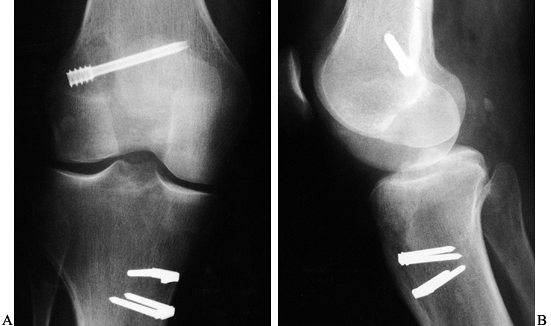

Figure 89.1. A:

Anteroposterior radiograph of a skeletally mature right knee with chronic ACL insufficiency. A healed Segond fracture is noted by the bony spur on the lateral tibial plateau’s lateral cortex, proximal to the fibula. B: Anteroposterior radiograph of a skeletally immature individual with a painful traumatic effusion. The x-ray reveals a lateral capsular avulsion, indicative of an injury to the ACL. |